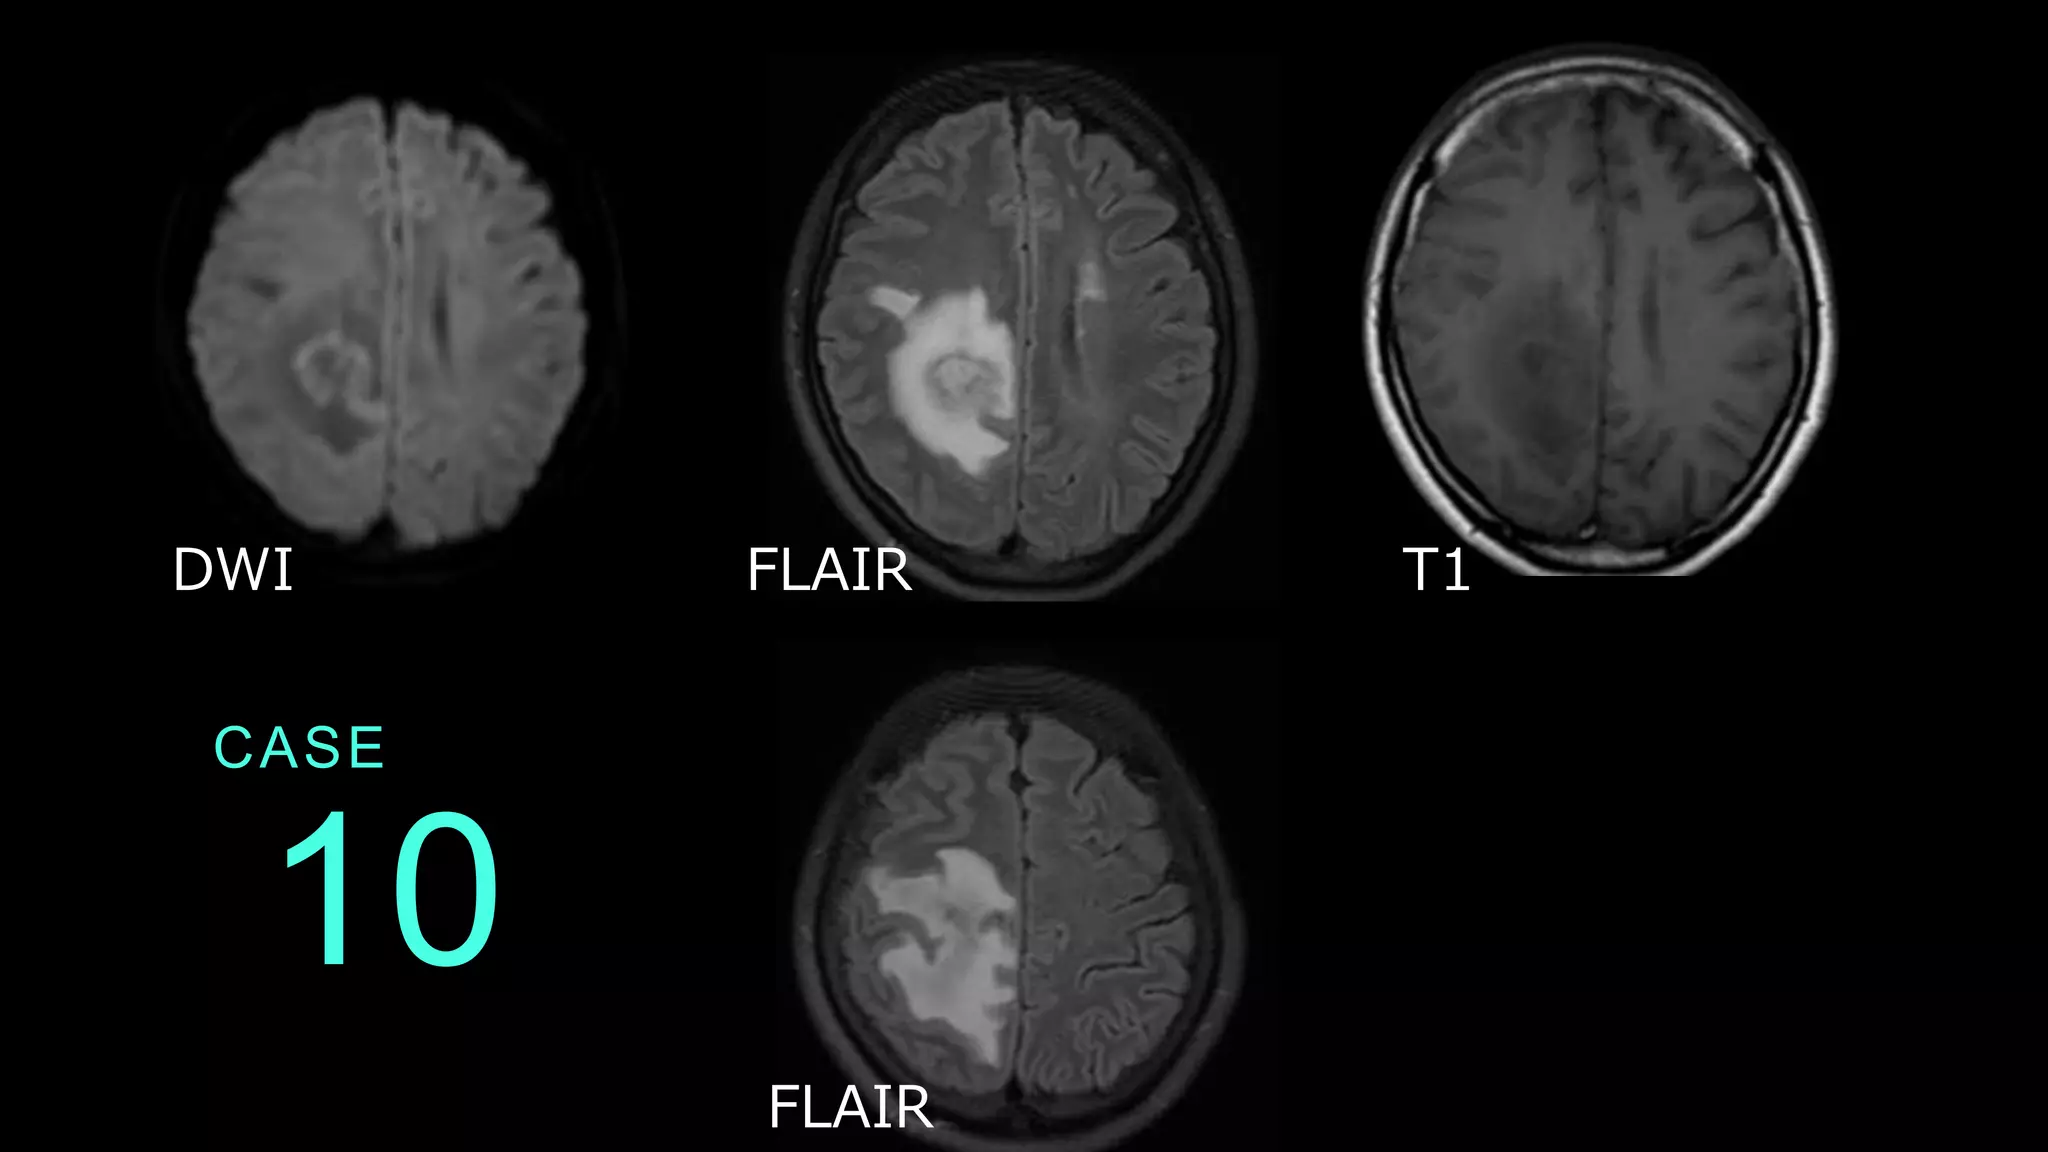

10 CASE DWI FLAIR T1 FLAIR

10 CASE DWIでは右側頭頂部に淡いLOWの病変あり。FLAIRで は内部にややHIGHの腫瘤性病変があり、その周囲の白 質に高信号病変がある。同病変はT1ではLOWである。 DWI FLAIR T1

10 CASE コメント:脳腫瘍症例。Mass effectといって、FLAIR HIGHで見える高信号病変が、腫瘤の周囲に認められる。